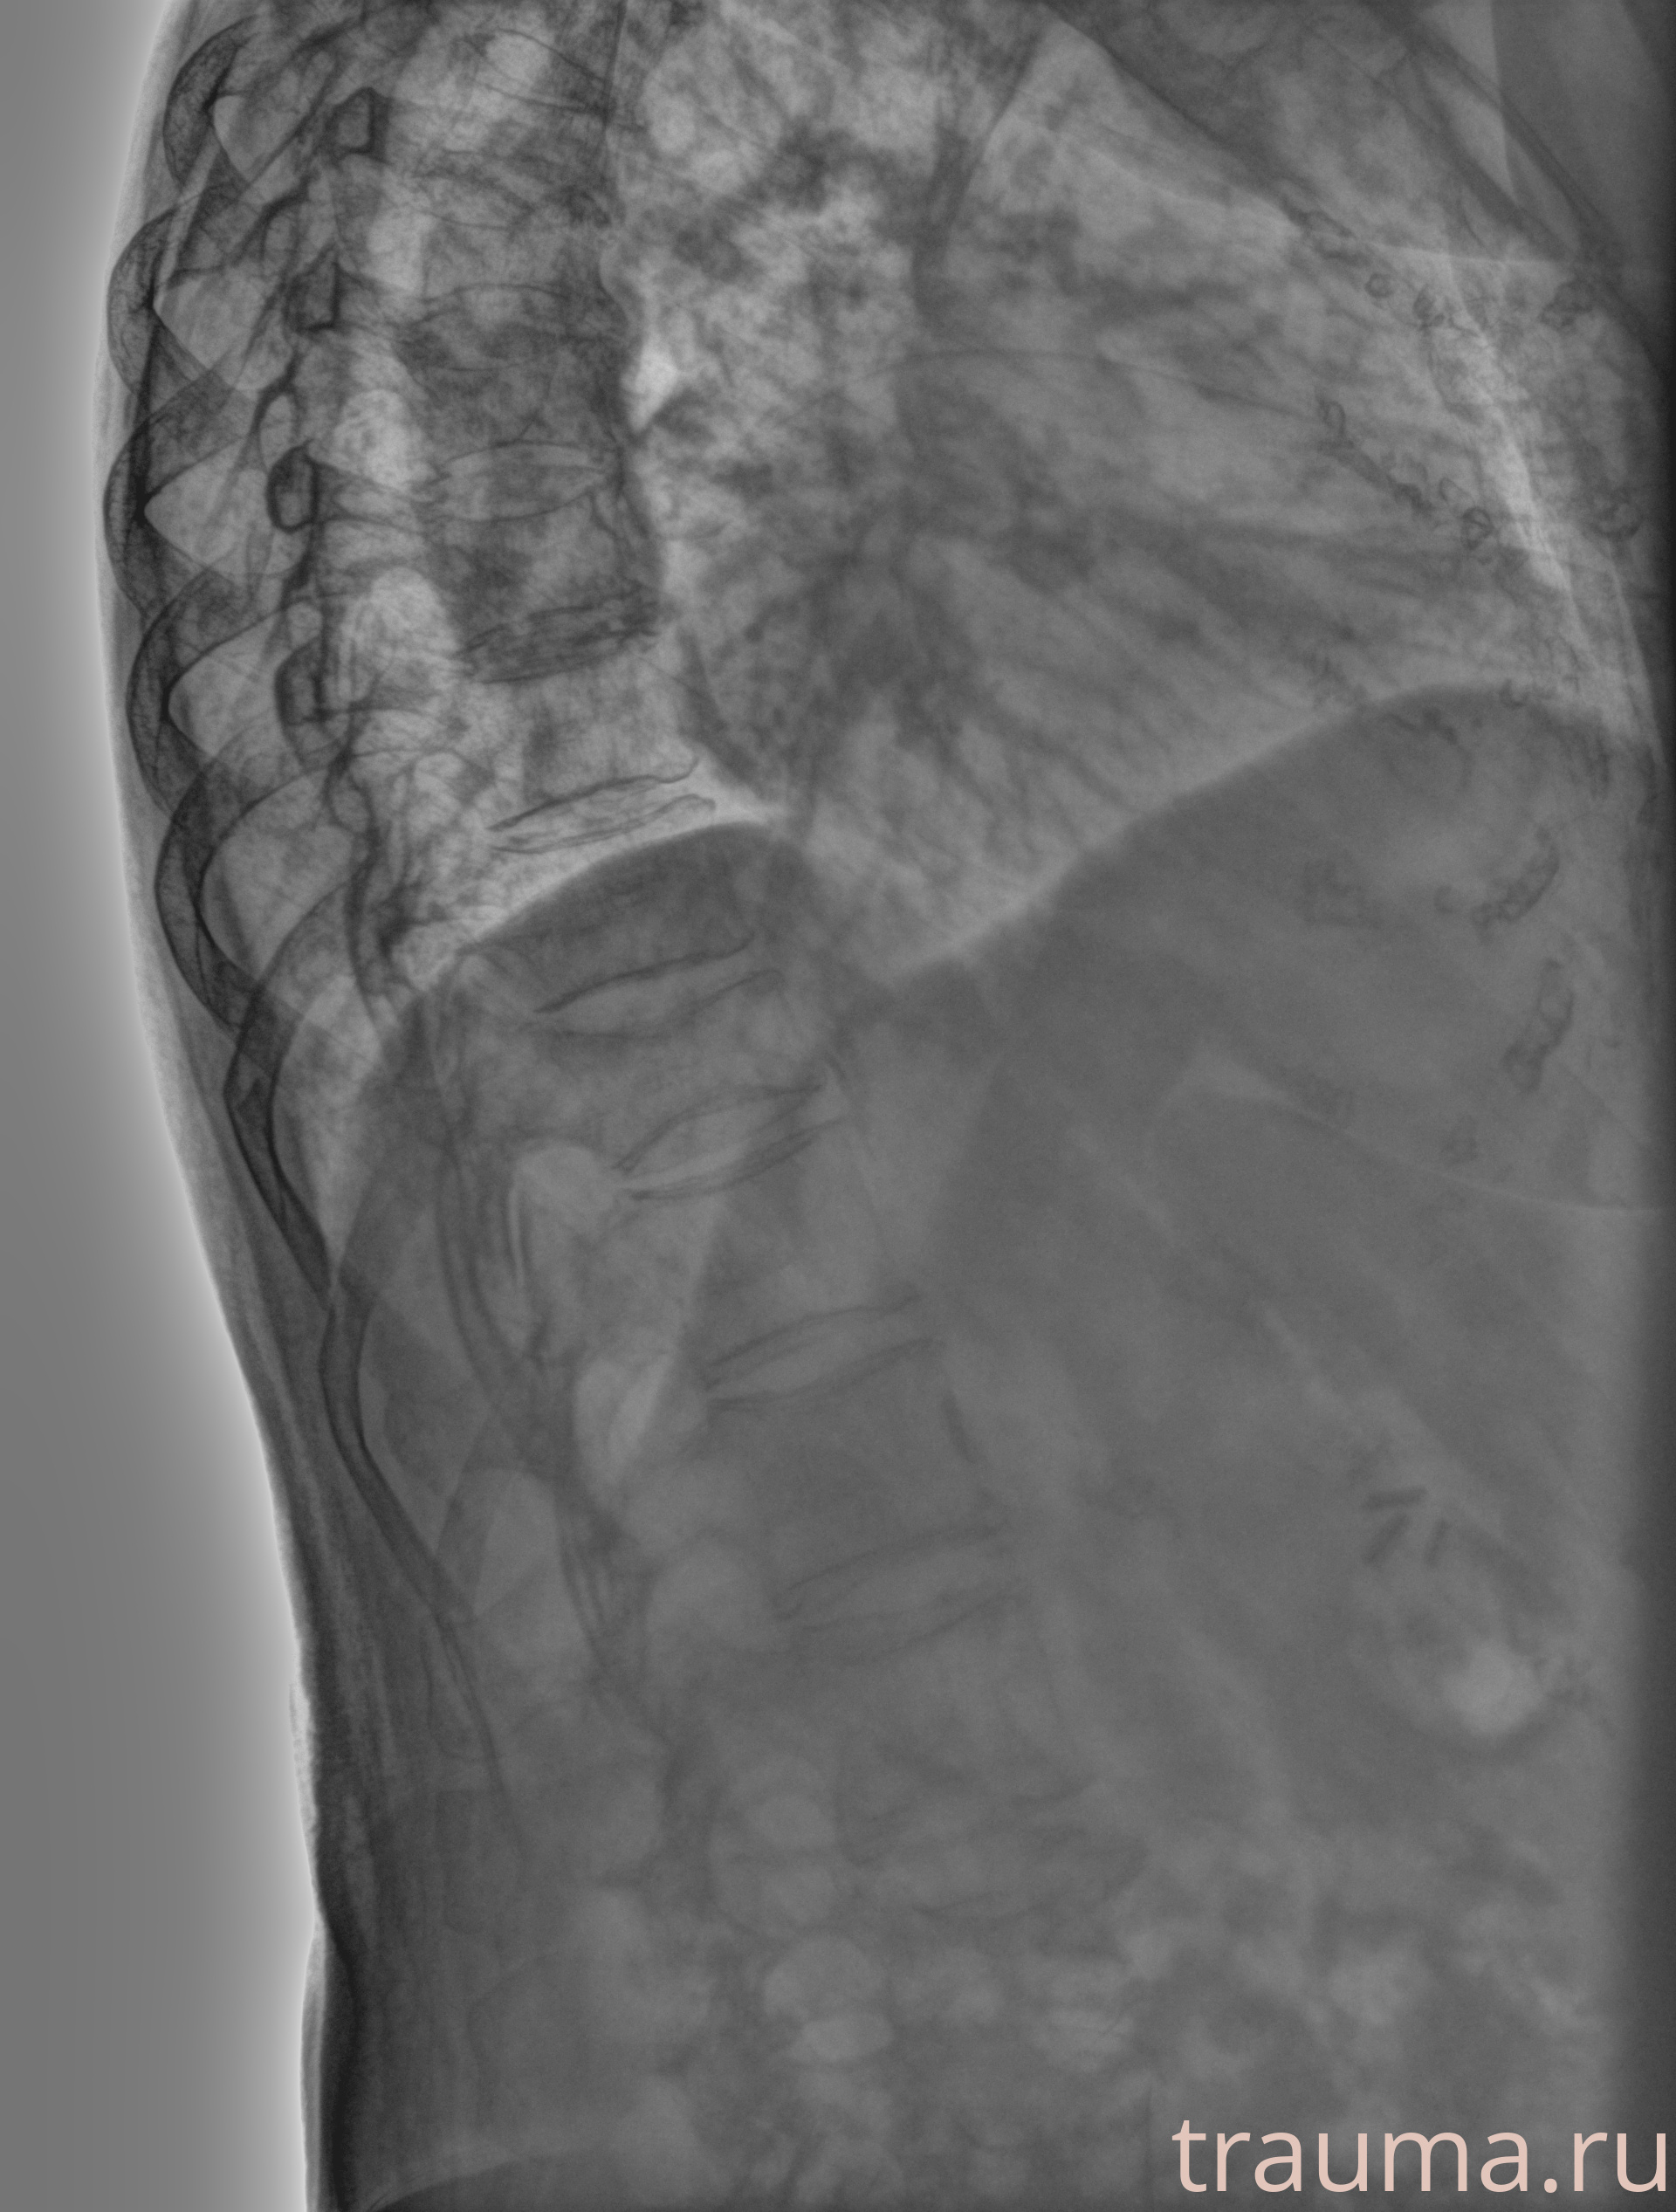

Рентгенограммы

Рентген на дому: по вашему адресу приезжает врач-рентгенолог, травматолог-ортопед с мобильным рентгеновским аппаратом, проводит диагностику травмы или заболевания, делает необходимые рентгенограммы, дает рекомендации по дальнейшему лечению. Получить качественные снимки в домашних условиях возможно благодаря уникальной методике, разработанной МосРентген Центром для института  Склифосовского